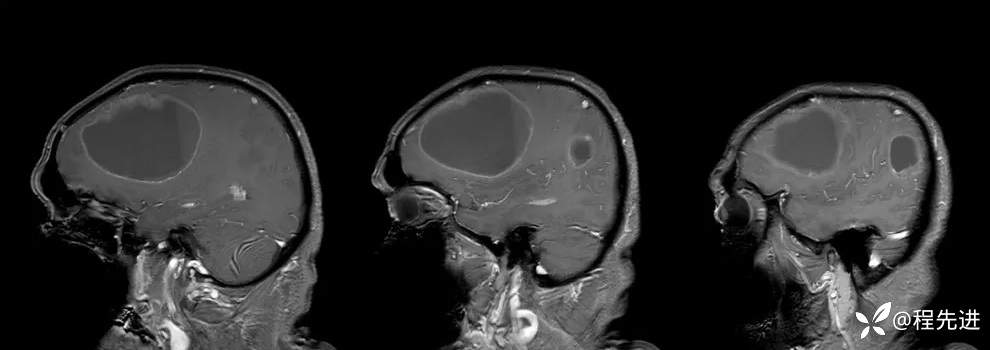

患者性别:男

患者年龄:65岁

简要病史:头痛、神志异常、行走不稳3周

实验室检查:未见明显异常

MRI平扫+增强:

T1增强: